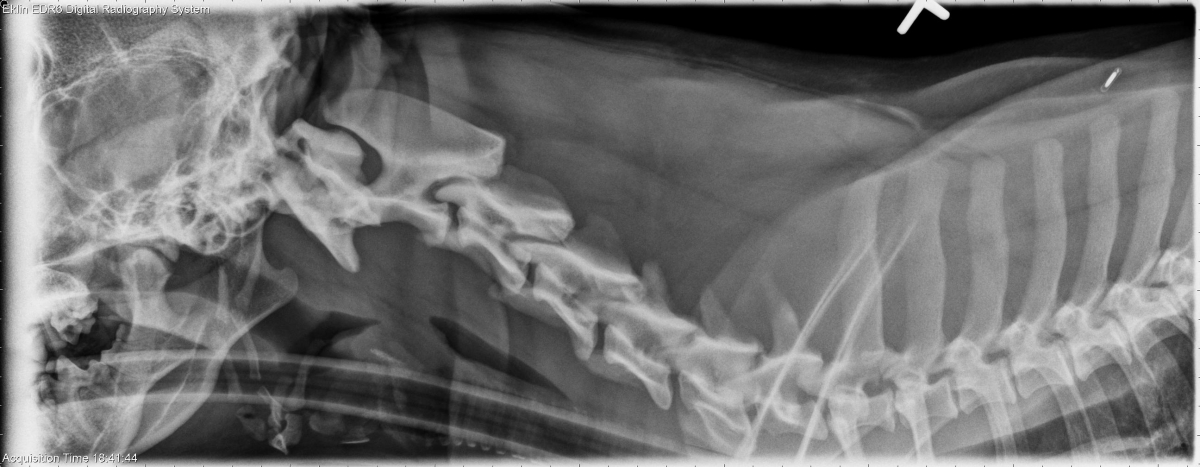

Today’s case is a 2-year-old female neutered Pit bull terrier. Fell off bed 10 days previously, acute paraparesis. What are your findings?

There is a fracture of the caudal end plate of the L4 vetebral body with adjacent sclerosis and lysis. There is ventral spondylosis deformans at this site. Mineral opacity material is present in the intervertebral foramen. The remainder of the vertebral bodies appear normal. On flexed and extended views, there is no evidence of instability.

Fracture and osteomyelitis. It is unclear which pathology is primary, and a migrating foreign body could also be involved.